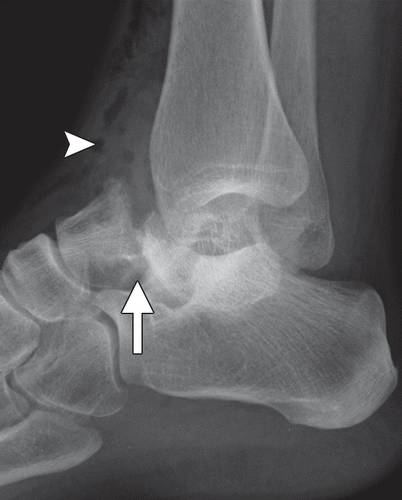

图10a粉碎性骨折冠状剪切距骨体断裂。 (a)该踝的外侧片显示距骨体(箭头)与在后距下关节突骨折碎片的冠剪切断裂。 (b)踝关节的AP射线照片显示后面小面(箭头)的揭示,与后股间关节的半脱位一致。 (c)矢状的CT图像显示了主要在冠状面中的距骨体的粉碎性骨折(箭头)。 在后距下关节处的骨折碎片存在前后牵引,导致半脱位(箭头)。

距骨体的剪切断裂通常由在高度跌倒或机动车辆事故的设置中的背屈脚上的轴向负载引起。 粉碎粉碎的距骨体外骨折对所有距骨损伤的预后最差(24)。 它们通常由于高能量冲击并且经常是开放性骨折。 骨丢失和非解剖复位的发生率高,并且随后出现缺血坏死。

初步诊断可以用放射线摄影,然后进行冠状和矢状重建到踝臼的CT,以评估粉碎,关节内累及手术计划(1,25,26)。